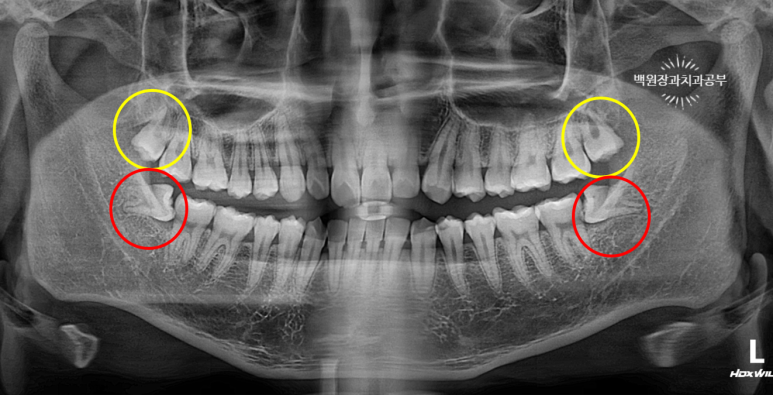

21세 남자 환자였습니다. 양쪽 아래 매복 사랑니가 존재하는 상태였어요.

수평 매복 상태 (horizontal partial impacted state) 였으며, 딱 봐도 뽑아야될 것 같아요!!

노란색 원으로 표시된 치아들이 위 사랑니 입니다. 상악 제3대구치라고도 불러요.

빨간색 원으로 표시된 치아들은 아래 사랑니 입니다. 하악 제3대구치라고도 불러요.